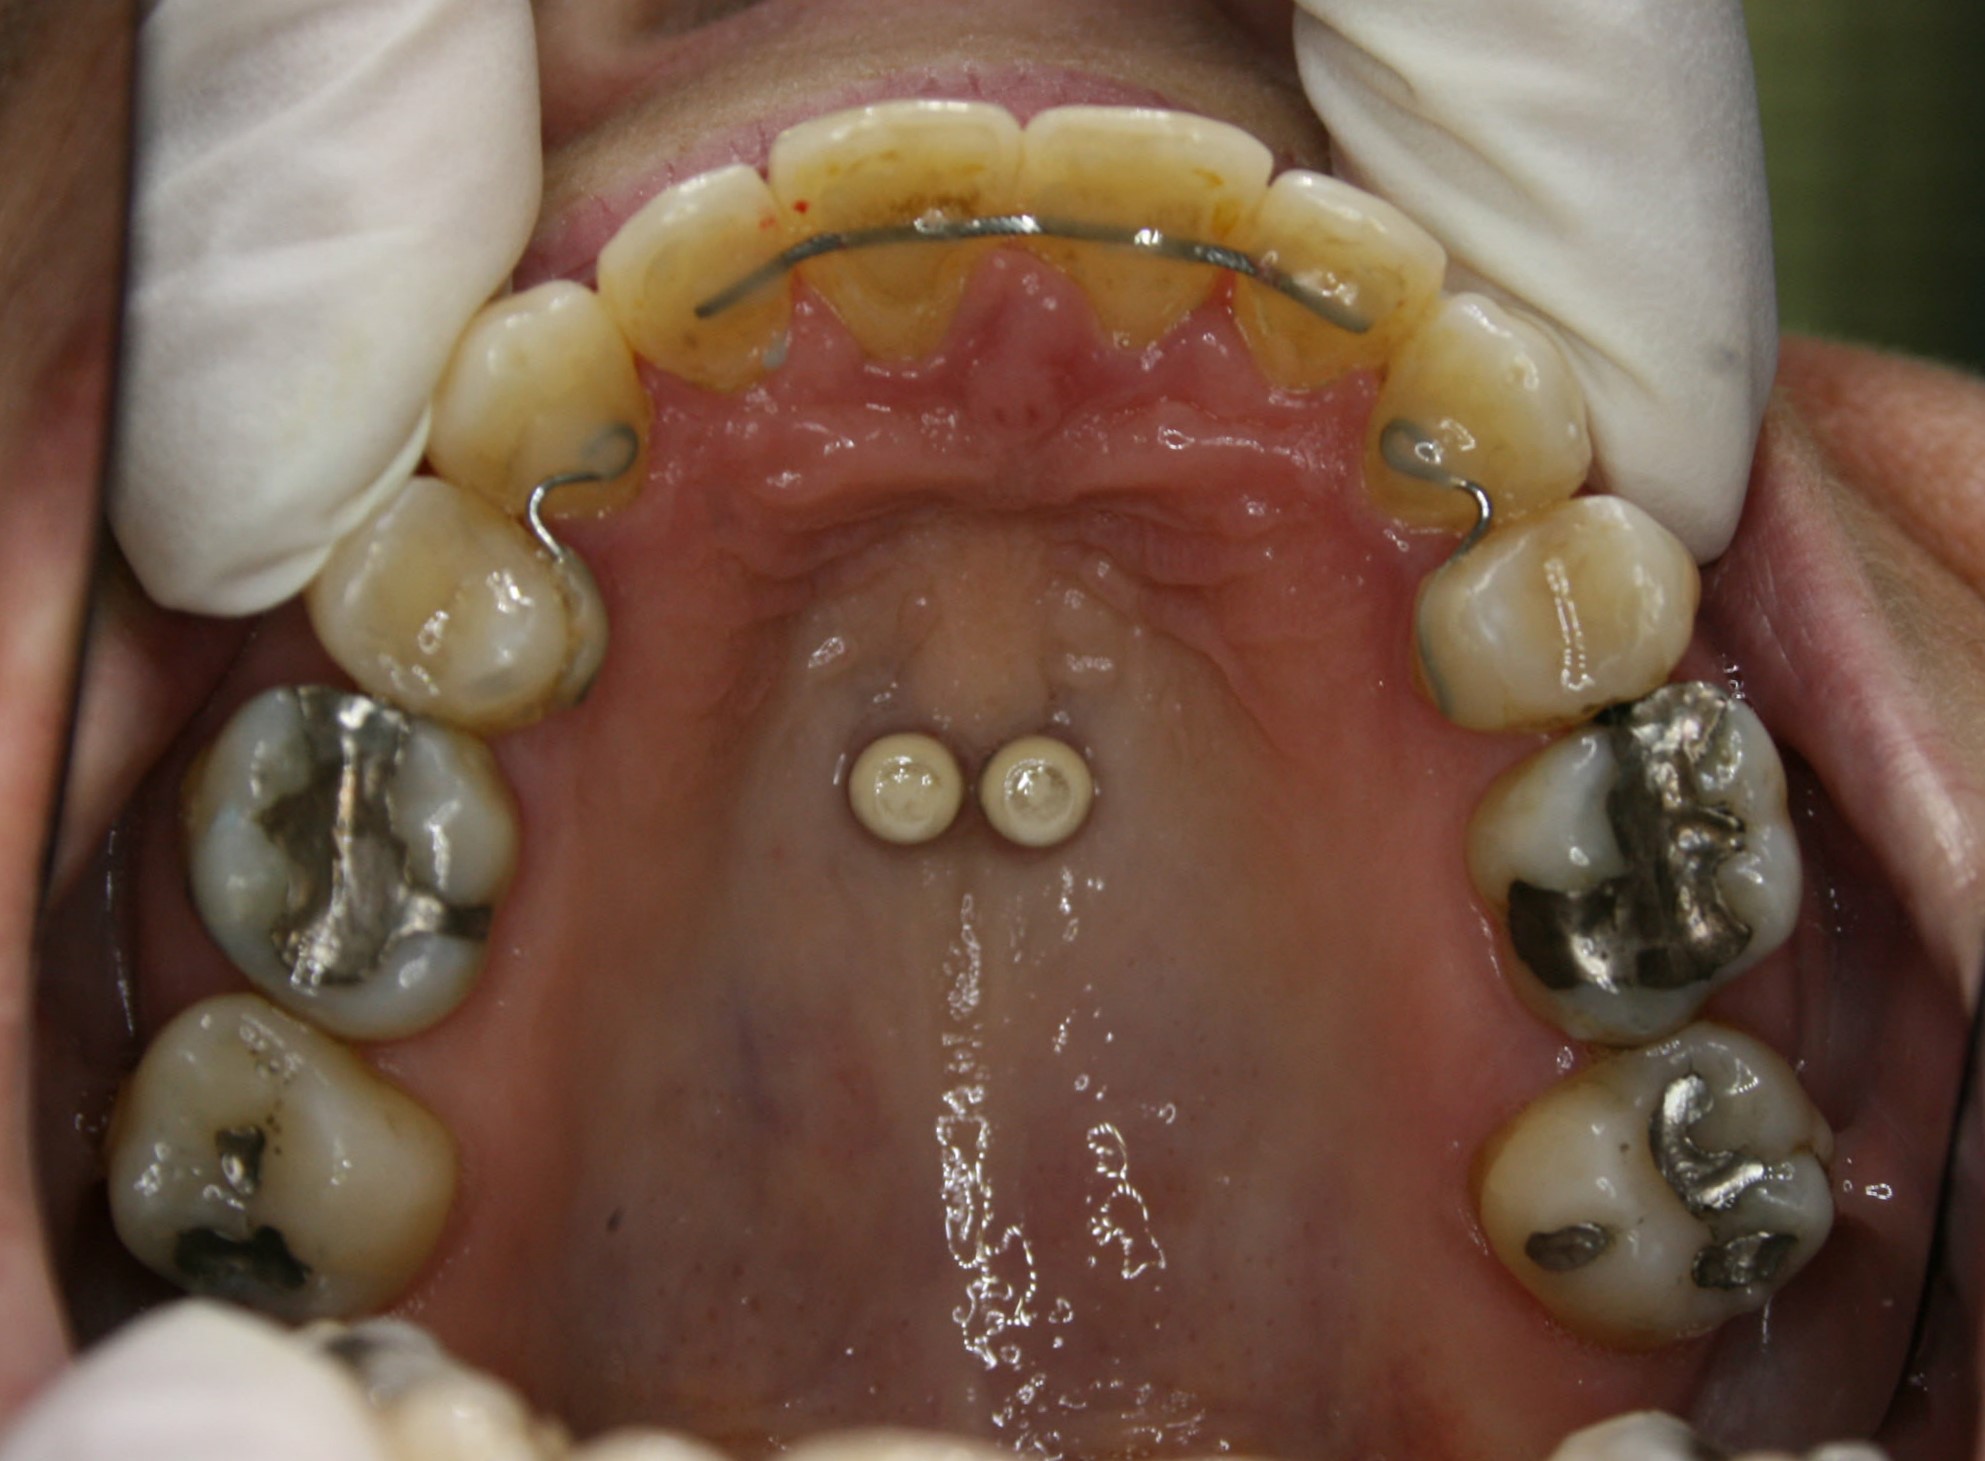

Während der Behandlung

Die ersten kleinen Backenzähne sind bereits entfernt und die festsitzende Zahnspange ist eingesetzt, in diesem Falle quasi unsichtbar auf der Innenseite der oberen Schneidezähne. Es ist wesentlich, daß die Lücken nur von vorne her geschlossen werden. Dies wurde sichergestellt, indem die Zähne hinter den Lücken über temporäre kleine Implantate am Gaumendach verankert wurden. In der Bildsequenz ist der Behandlungsfortschritt zu erkennen; der Lückenschluß war nach 1½ Jahren erreicht.

Im Unterkiefer kam auch eine auf der Innenseite der Zähne befestigte Zahnspange zum Einsatz; da es keine Lückenschlußaufgabe zu bewältigen gab, konnte ein einfacheres System verwendet werden. Es ist angenehmer für die Zunge, weil es flacher ist als das aufwendigere System im Oberkiefer. Siehe hierzu auch die Ausführungen im Abschnitt „Behandlungsmethoden – Welche Arten von Zahnspangen gibt es". Die Ausformung des Unterkiefers war nach einem Jahr und 2 Monaten abgeschlossen.